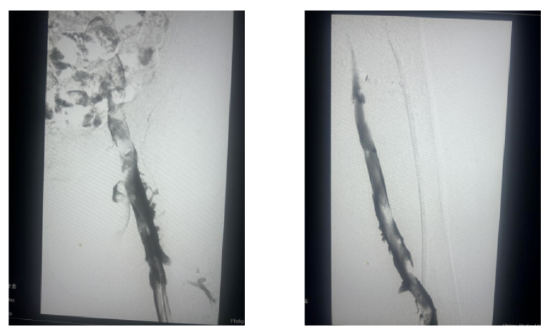

图左:造影显示左髂静脉大量血栓,显影不良 图右:抽吸后左髂静脉显影

图片尺寸550x334